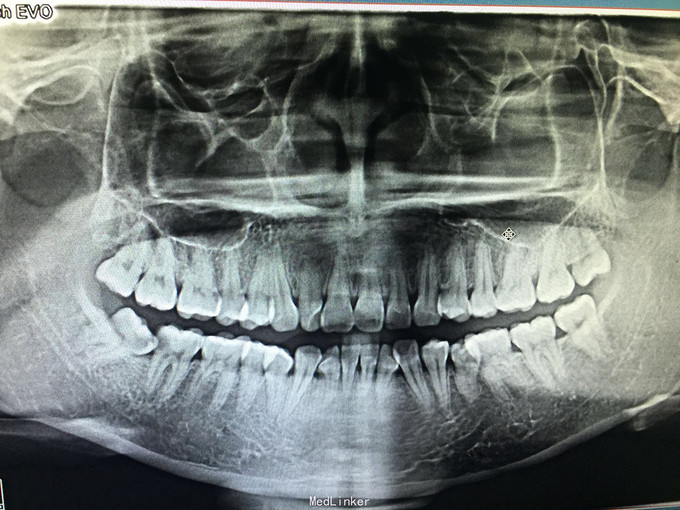

临床检查:48未完全萌出,盲袋附着无溢脓,47合面无明显龋坏,远中邻面探(++),冷(++),叩(-),松动度(-),牙周正常. 辅助检查:X线示48近中阻生,47龋坏累积髓腔,根尖周牙周膜增宽。

诊断:47牙髓炎,48阻生齿。 治疗:经患者知情同意后,47局麻去腐降牙合,开髓拔髓寻找根管口,建立直线通路,扩通根管,确定工作长度。S3/EDTA凝胶镍钛器械,低浓度次氯酸钠冲洗根管,预备至25/06,氢氧化钙诊间封药,48翻瓣拔除,缝合。一周后复诊,试主尖X线示恰充,试干根管,导AH-PLUS糊剂,热压胶垂直加压根充,术后见根管恰充,暂封观察嵌体修复。拔牙创拆线。

对于无意义的阻生齿要尽早拔除,以免危害其他牙齿。